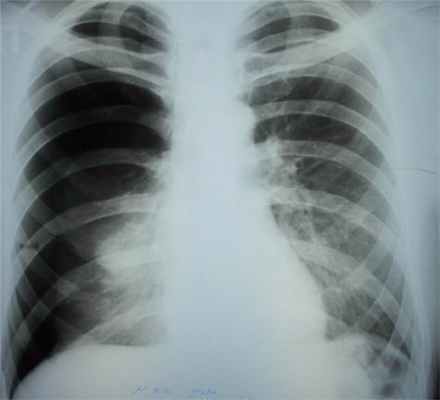

Как правило, диагноз ПСП ставят с помощью обычного рентгеновского снимка грудной клетки, хотя специалист может также определить наличие ПСП при прослушивании легких. В некоторых случаях может быть назначена компьютерная томография (КТ), если лечащему специалисту требуется более детальное изображение ваших легких.

- на данных рентгенологического обследования, компьютерной томографии:

Рентгенологическое исследование структуры легких с целью диагностики различных патологий.

Спонтанный пневмоторакс развивается, как правило, у мужчин молодого возраста, у женщин он встречается в 5 раз реже. Первый момент от развития пневмоторакса пациенты чаще жалуются на боль в грудной клетке на стороне пневмоторакса колющего или ноющего характера, ощущение затрудненного дыхания, кашель, как правило, сухой, снижение переносимости физической нагрузки. Через несколько дней часто появляется повышение температуры тела. Диагноз чаще не вызывает затруднений у опытного специалиста. При обзорной рентгенографии грудной клетки в двух проекциях в большинстве случаев удается установить диагноз.

Обязательно при пневмотораксе назначают рентген. По его результатам доктор определяет диагноз. Дополнительно может быть взята пункция из плевральной полости с газом или воздухом. Давление при этом в ней отсутствует.